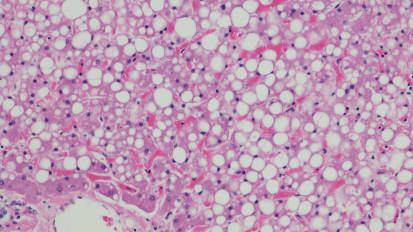

After the Cure: What comes next for patients with post-HCV liver fibrosis?